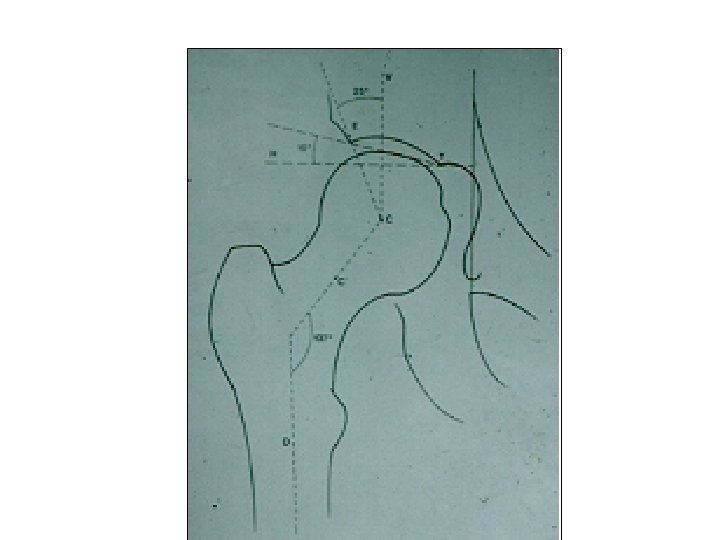

SEMIOLOGIE DE LA HANCHE 3°Signes d’examen (signes physiques): Etude des mouvements Mouvements passifs+++: le

SEMIOLOGIE DE LA HANCHE 3°Signes d’examen (signes physiques): Etude des mouvements Mouvements passifs+++: le coxogramme Mouvements combinés Mouvements actifs

SEMIOLOGIE DE LA HANCHE 3°Signes d’examen (signes physiques): Etude des mouvements Mouvements passifs+++: le coxogramme flexion/extension/abduction/adduction RE/RI Mouvements combinés Mouvements actifs : étude des muscles et des tendons: le moyen fessier++ 4° Examen régional: neurologique amyotrophie